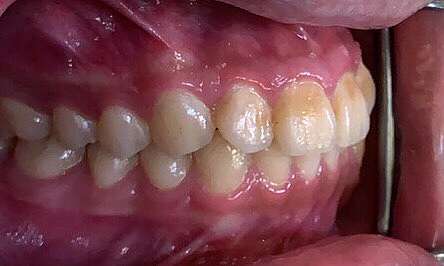

下顎骨骨折 Mandibular Fracture 蔡佩晏醫師的矯正故事 打造你的微笑曲線專家 Dr Tsai S Blog 痞客邦

口腔顎面外科 下顎骨骨折 經典牙醫 大紀元